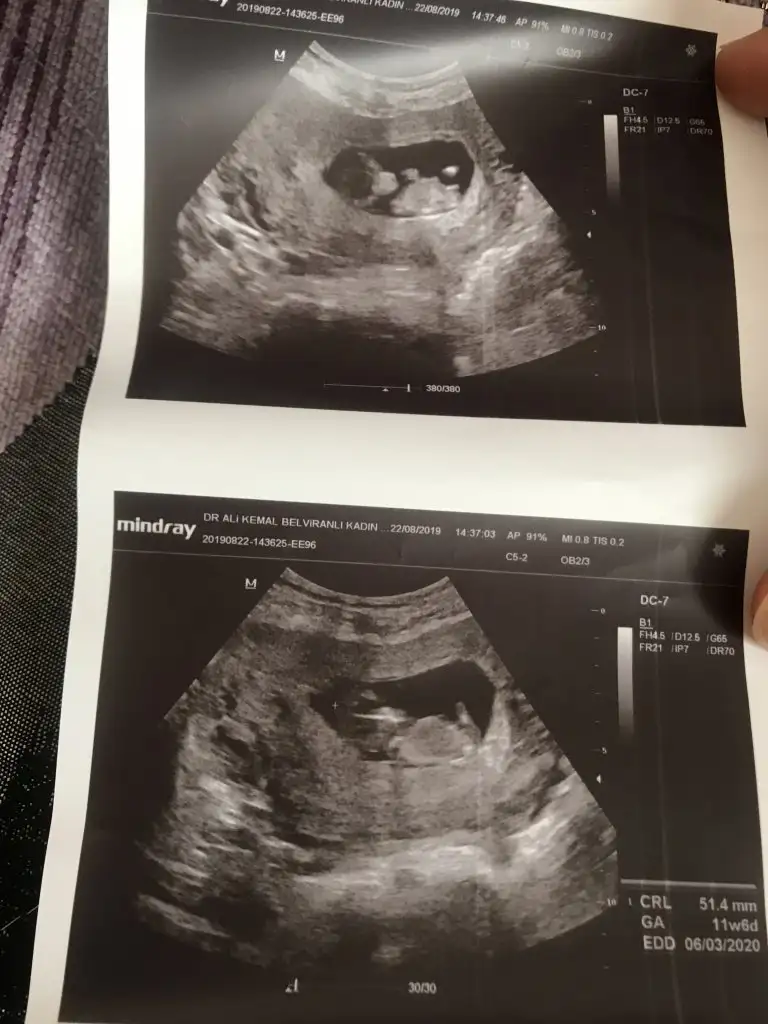

Kıza benzettim benSelamün aleyküm kızlar nasılsınız ?benim 2 kz 1 oğlum var.en küçüğüm daha 15 aylık kız.plansız bir şekilde tekrar hamile kaldım şuan 11-6 günlük hem kızımda hem oğlumda tahminleriniz tutmuştuşimdide tahmin istiyorum sizlerden bana erkek gibi geldi

Selamün aleyküm kızlar nasılsınız ?benim 2 kz 1 oğlum var.en küçüğüm daha 15 aylık kız.plansız bir şekilde tekrar hamile kaldım şuan 11-6 günlük hem kızımda hem oğlumda tahminleriniz tutmuştuşimdide tahmin istiyorum sizlerden bana erkek gibi geldi